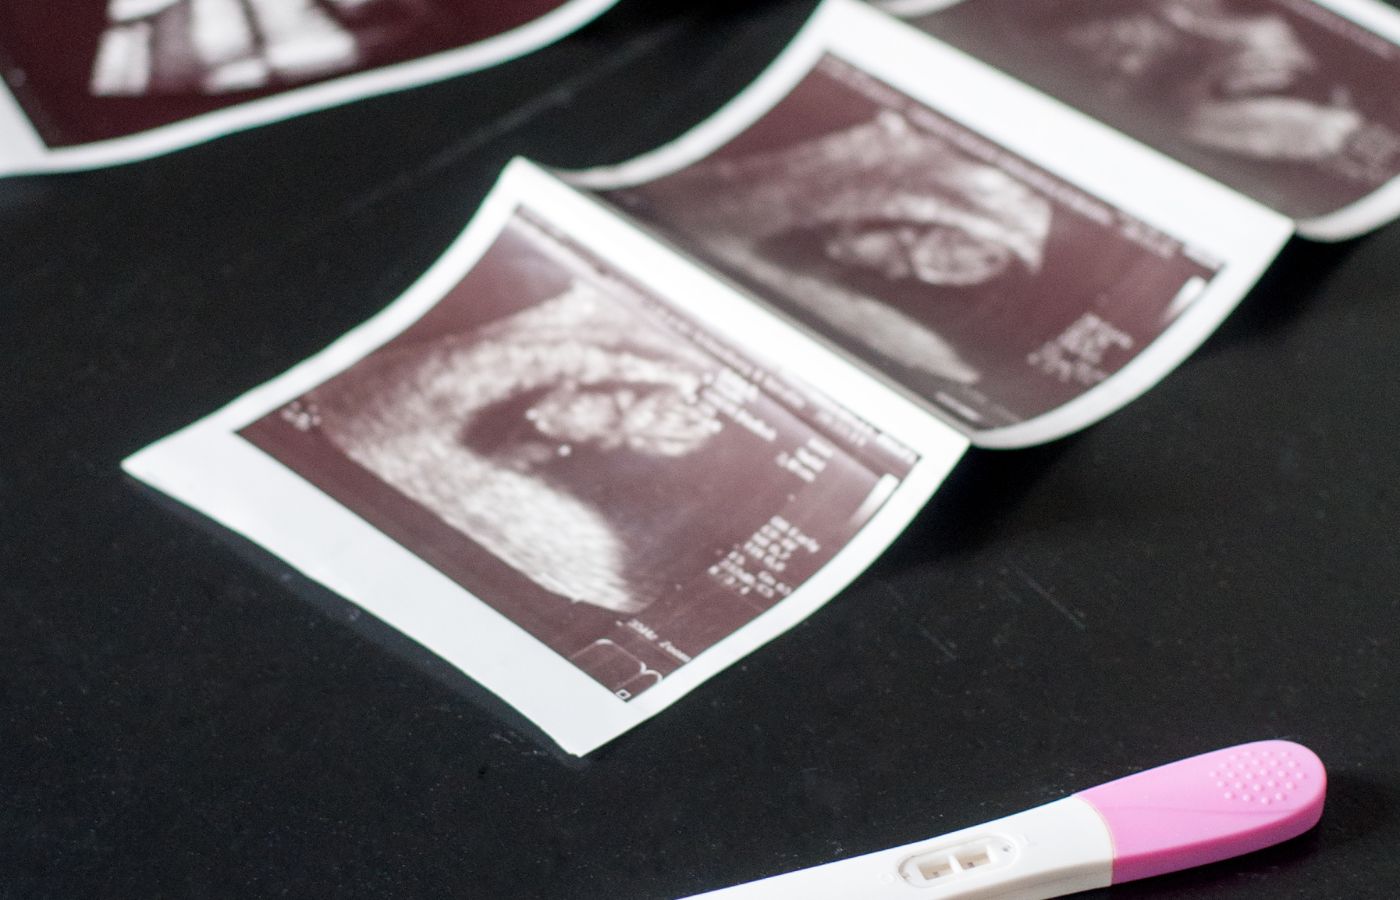

Pregnancy is one of the most beautiful and transformative journeys in a woman's life. During this period, it’s essential to ensure that the baby’s development is progressing smoothly. One of the most important diagnostic tools to monitor fetal growth and development is the USG Growth Scan (Ultrasonography). This non-invasive imaging technique plays a vital role in monitoring the health of both the baby and the mother. In this blog, we’ll explore the significance of the USG Growth Scan in pregnancy, the types of ultrasound in pregnancy, and how you can find a reliable sonography centre near me or USG center near me for your check-up.

A USG Growth Scan is an advanced form of ultrasound used to track the growth and development of the fetus throughout pregnancy. It helps in assessing the baby’s size, position, and overall well-being. This scan is particularly important in the second and third trimesters to monitor any growth abnormalities or complications that may arise. A sonography near me can provide the essential services you need for such tests, offering detailed insights into fetal development.